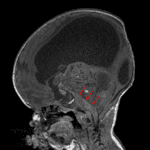

- Large, heterogeneous mass centered in the quadrigeminal plate region measuring 6 x 2.8 x 6 cm

- Extensive corresponding mass effect on the midbrain with effacement of the cerebral aqueduct and associated severe obstructive hydrocephalus with cerebral parenchymal thinning

- Additional noncontiguous masses in the left cerebellopontine angle cistern and along the ependymal margin of the frontal horn of the left lateral ventricle at the caudothalamic groove

- The above described masses demonstrate areas of restricted diffusion (particularly the two smaller lesions) but no discrete enhancement